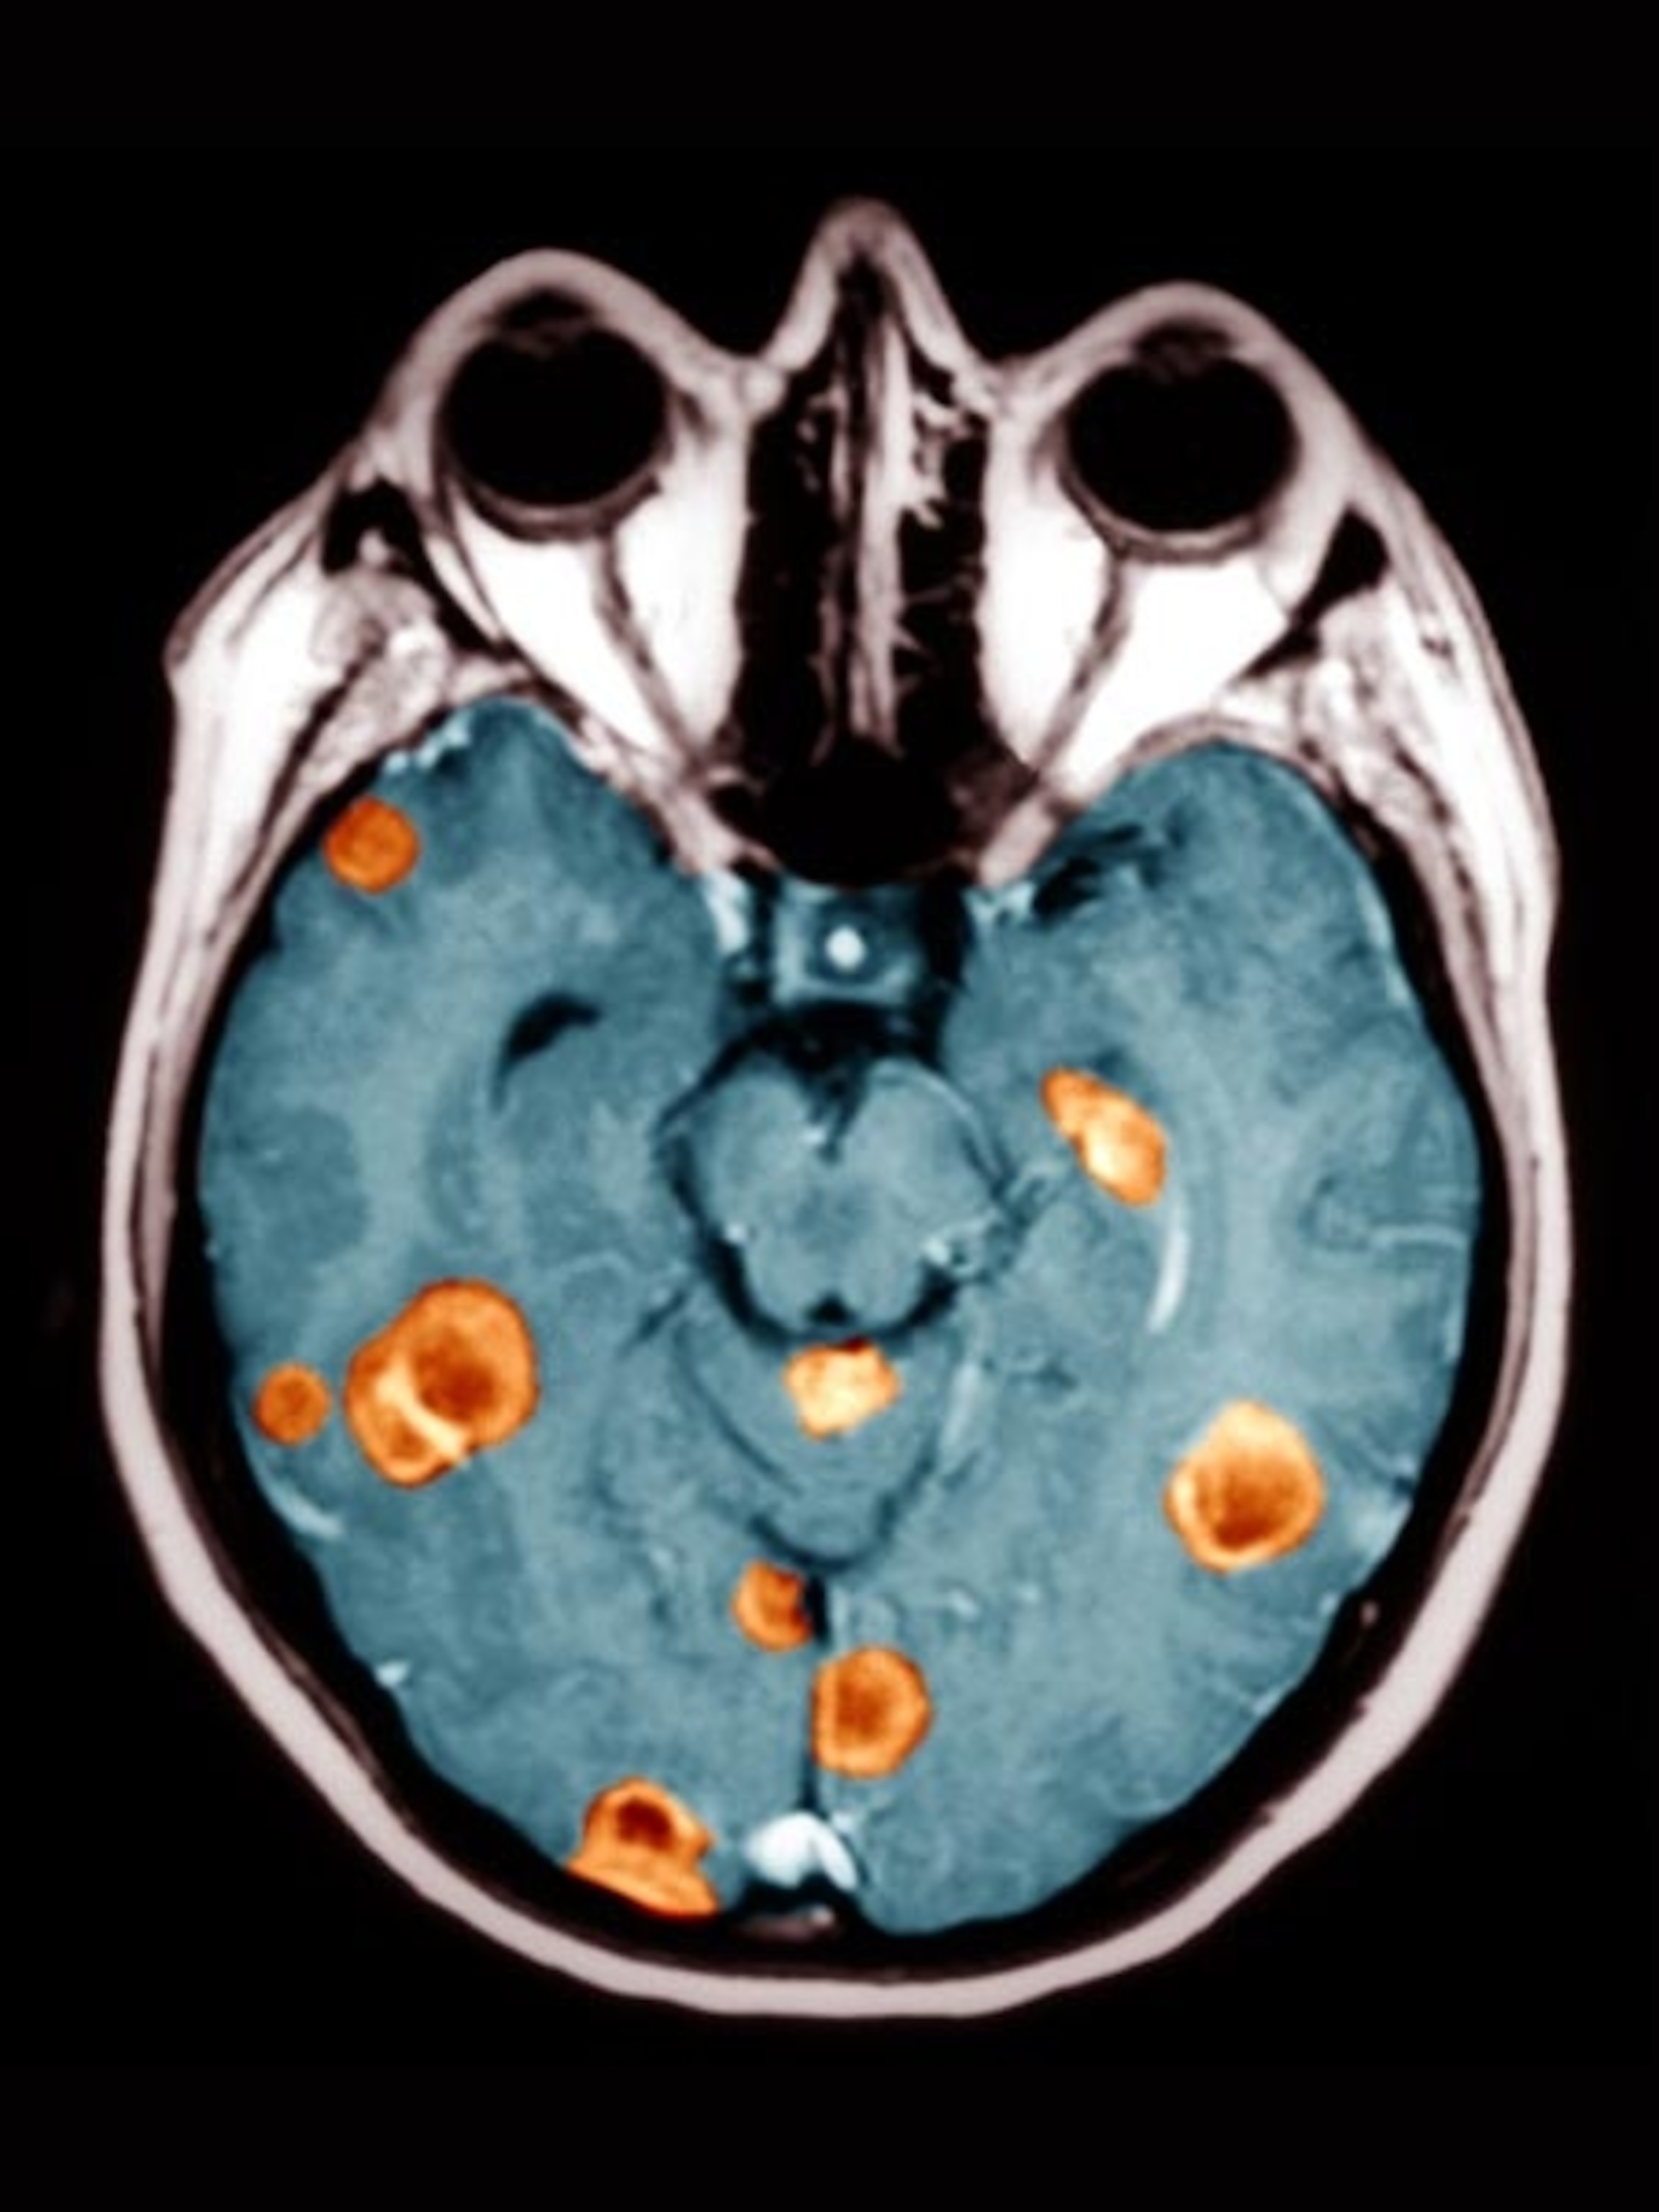

The study team determined that the ancient growth was a kind of bone cancer called a periosteal osteosarcoma—one that “looks almost exactly like osteosarcoma in humans,” says coauthor Patrick Asbach, a medical doctor and radiologist at Berlin’s Charité University of Medicine. This specific type of bone cancer afflicts about 800 to 900 of the 3,450 or so people who are diagnosed with skeletal cancers each year in the U.S. today.

Among them was a thighbone with a puzzling growth that came to Haridy’s attention last summer. She then recruited Asbach to help conduct a micro-CT scan to look inside the fossil bone and see its internal structure, which allowed the team to determine the type of cancer involved.

Related Photos: Understanding Cancer